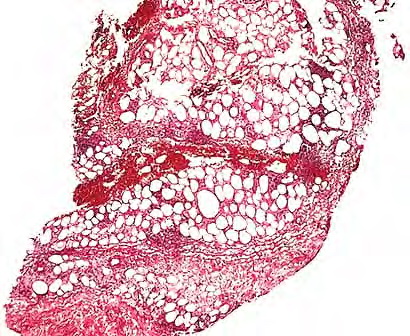

The infection begins as a subcutaneous nodule exhibiting "ghost" ischemic-type dermal collagen and fat necrosis with deposition of fibrin and hematoxyphilic extracellular clumps of mycobacteria. Ulceration proceeds as the epidermis loses its vascular supply. Ziehl-Neelsen stains reveal vast numbers of acid-fast bacilli in the necrotic fat ; their distribution is often irregular. A variable degree of neutrophil infiltration and thrombosis of vessels are also observed. In time, a nonspecific granulation tissue or a granulomatous reaction commences from the depth and sides of the ulcer; healing and re-epithelialization take place with considerable scarring. Acid-fast bacilli decline rapidly in number during healing . The histopathologic case definition for Buruli ulcer, useful for research studies, is (a) the typical pattern of infarctive­like necrosis of deep dermal collagen and fat and (ideally, but not always found in limited samples) (b) nearby clusters of acid-fast bacilli.